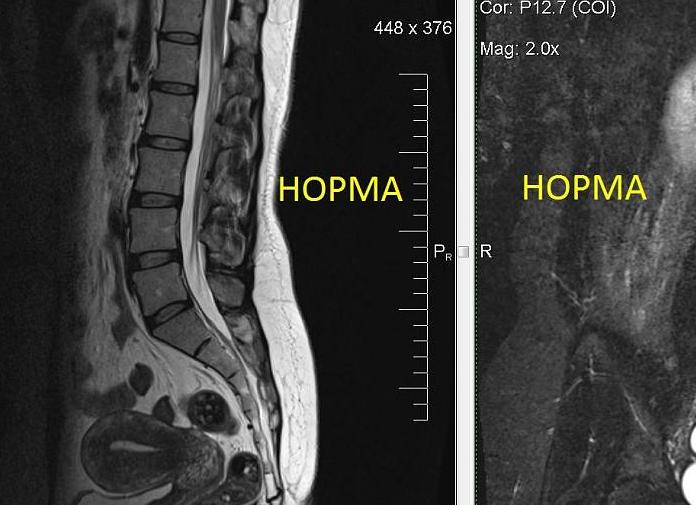

Мрт грыжа поясничного отдела

Межпозвоно́чная грыжа (межпозвонко́вая грыжа, грыжа межпозвоночного диска) — это смещение пульпозного ядра межпозвоночного диска с разрывом фиброзного кольца. Наиболее часто встречаются грыжи межпозвонковых дисков пояснично-крестцового отдела позвоночника (150 случаев на 100 000 населения в год), значительно реже наблюдаются грыжи в шейном отделе позвоночника, наиболее редки — в грудном отделе. Хотя грыжи относительно редко требуют хирургического вмешательства, тем не менее в США ежегодно проводится более 200 тысяч, а Германии 20 тысяч вмешательств. В 48 % случаев грыжи локализуются на уровне L5-S1 пояснично-крестцового отдела, в 46 % случаев — на уровне L4-L5, остальные 6 % на других уровнях или на нескольких уровнях пояснично-крестцового отдела.